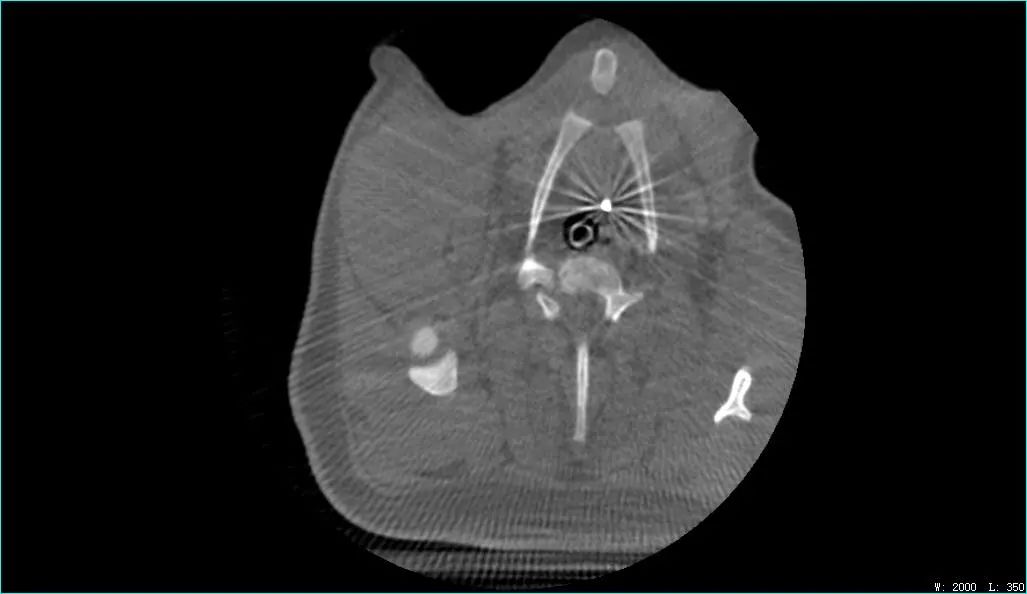

DSA影像图

澎立检测以专业高效的服务品质配合严谨务实的科学态度专注于医疗器械研发阶段--临床前动物实验;提供体内结合体外分析(组织病理及药物代谢分析)整体化医疗器械临床前动物实验服务,并且在原有心脑血管、骨科、牙科、有源器械服务领域基础上,开拓结构性心脏病,手术机器人等新领域平台的搭建,满足医疗器械创新研发的需要,助力医疗器械企业产品研发、推广、上市。